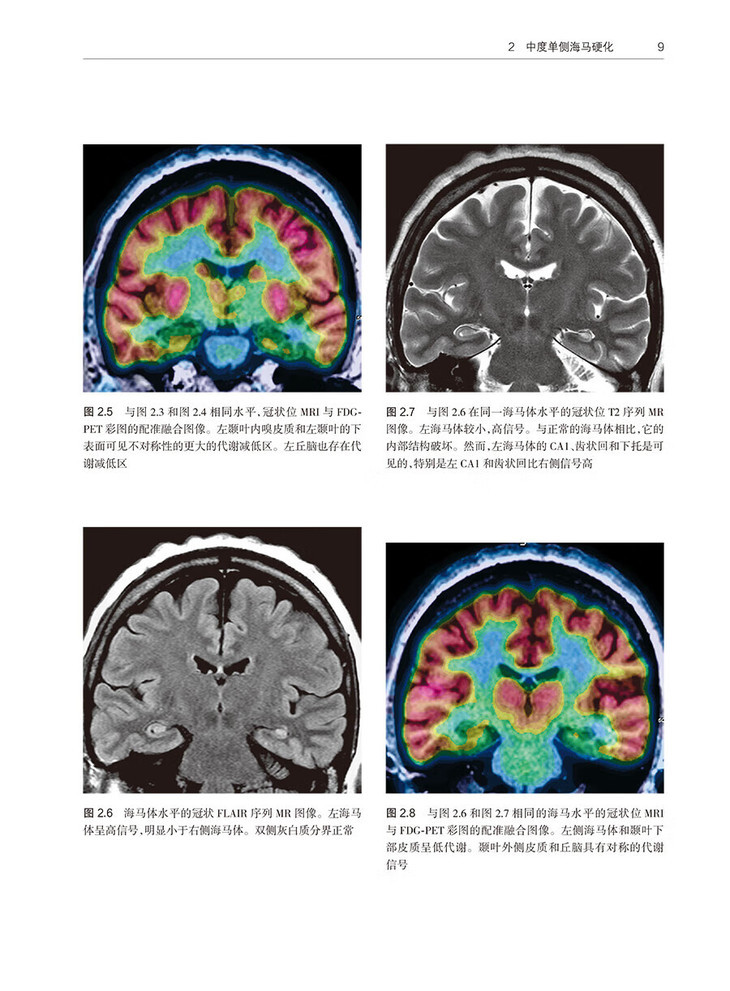

2 中度单侧海马硬化 /7